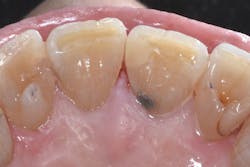

A 47-year-old female patient was scheduled for a composite restoration on the mesiolingual of tooth No. 8 (figure 7). After caries removal and rubber dam placement, 37% phosphoric acid was applied to the entire preparation for 15 seconds, and then rinsed off (figure 8). A Mylar strip was positioned and stabilized with a V-Wedge (Triodent), and a universal adhesive was applied (figure 9). SureFil SDR flow+ in shade A2 was placed in a single increment, allowed to self-level and self-adapt for approximately 5 seconds, and then light cured for 20 seconds. The rubber dam was removed, and after checking occlusion and polishing the restoration, the patient was released (figure 10).